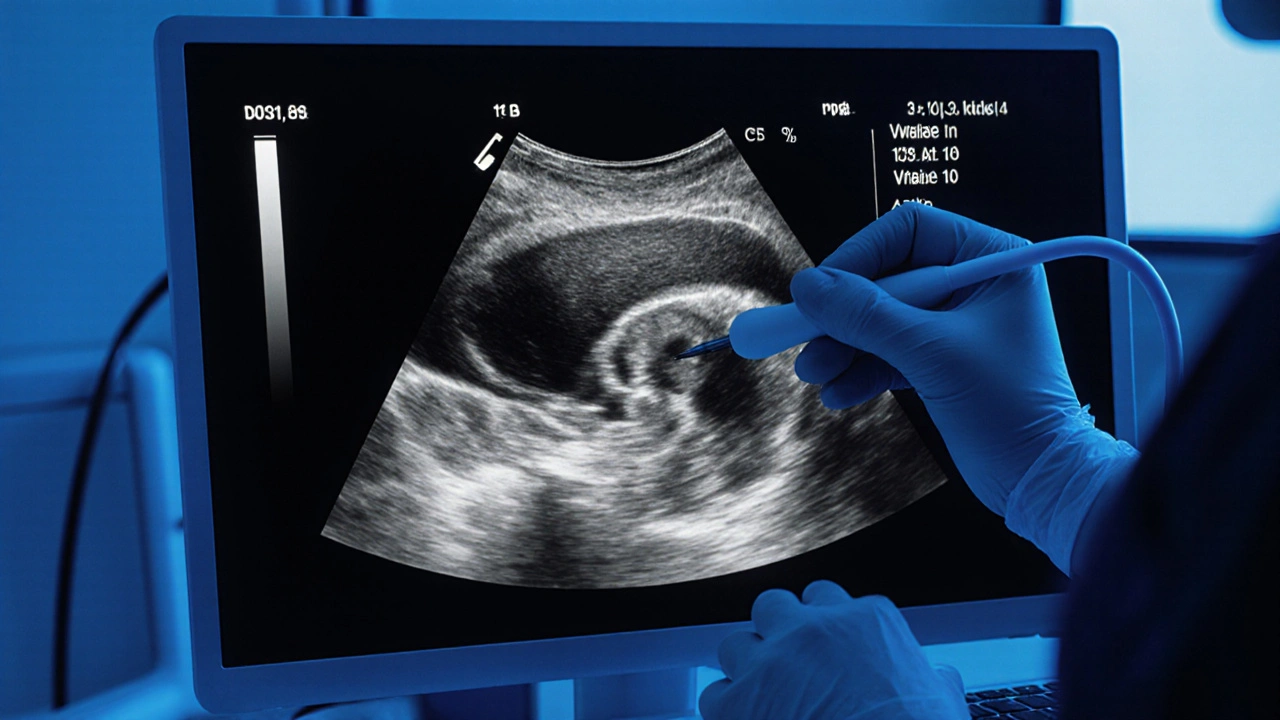

Transvaginální ultrazvuk - klíčový nástroj

Nejčastějším dalším krokem je transvaginální ultrazvuk. Tento test není bolestivý - pouze trochu nepříjemný. Gynekolog vloží sondu do pochvy, která vydává zvukové vlny a vytváří detailní obraz vaječníků. Na obrazovce vidí, zda je vaječník jednoduchý (například s jednou tekutinou plnou cystou) nebo složitý (s pevnými oblastmi, nádorovými výrůstky, krevními cévami uvnitř).

U zdravého vaječníku je struktura rovnoměrná. U nádoru se objevují nepravidelnosti - hranice nejsou hladké, vnitřek má různé hustoty, v některých případech i krevní proudění v nádoru. Gynekolog si poznamenává velikost, tvar, strukturu a přítomnost kapaliny v břiše (ascites), která může být příznakem pokročilého onemocnění. Tento obraz neříká, zda je to rakovina, ale ukazuje, zda je potřeba jít dál.

Obraz transvaginálního ultrazvuku ukazuje nepravidelné vaječníky s podezřelými strukturami.